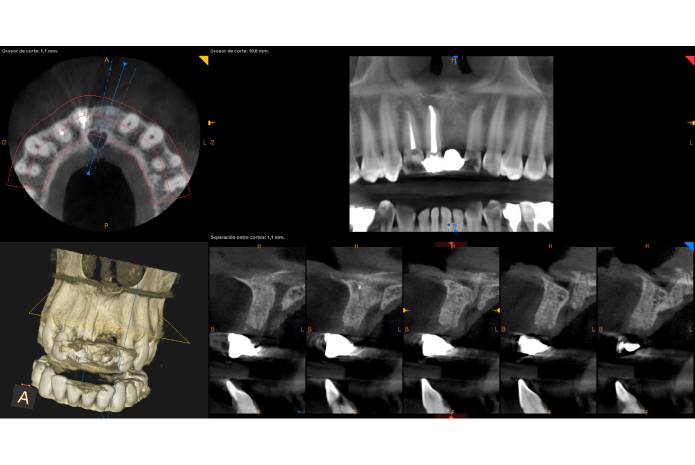

50% después de la misma. Por esta razón, en los casos que requieren de exodoncias en el sector estético anterior, siempre que sea posible, nuestra primera opción de tratamiento será realizar algún tipo de intervención, con el fin de mantener la arquitectura de los tejidos presentes o de mejorar los tejidos duros y/o blandos, y así favorecer las condiciones anatómico y biológicas futuras, para la colocación temprana o tardía del implante (1-5).

Esta primera opción de tratamiento cuando sea posible siempre será un implante inmediato después de la exodoncia y provisionalización inmediata, pero en aquellas situaciones clínicas en las que no podamos realizar una Implantología inmediata, deberemos de conocer y controlar qué acciones terapéuticas tenemos a nuestro alcance. Para ello, disponemos de varias alternativas quirúrgicas, como la preservación/reconstrucción del reborde alveolar con biomateriales de lenta reabsorción o injertos autólogos estructurados (6, 7), el uso de membranas reabsorbibles o barreras no degradables, técnicas de preservación de porciones vestibulares de raíces dentales y procedimientos de sellado alveolar mediante injertos autólogos, sustitutos tisulares y/o provisionalización (8-12).